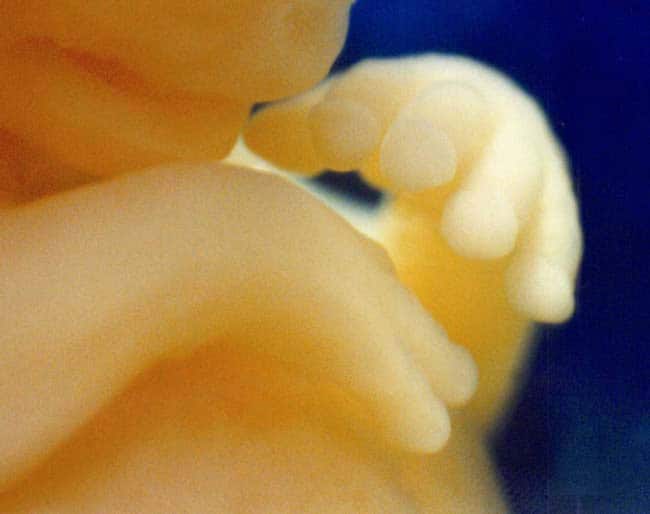

Το έμβρυο δείχνει προτίμηση είτε για το δεξί είτε για το αριστερό του χέρι καθώς κινείται μέσα στη μήτρα.

Ενώ το έμβρυο χρησιμοποιεί τόσο το αριστερό όσο και το δεξί του χέρι, όταν προσεγγίζει μικρούς στόχους, όπως τα μάτια και το στόμα του, το κάνει πιο γρήγορα και με μεγαλύτερη ακρίβεια όταν χρησιμοποιεί το κυρίαρχο χέρι του.